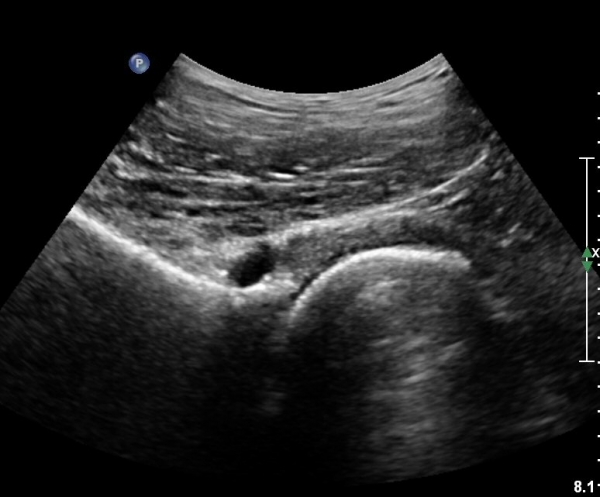

[¾ûµ¢ÀÌ] ¾ûµ¢ÀÌ °üÀý¼ø ÆÄ¿­ÀÇ ÃÊÀ½ÆÄ°Ë»ç(ultrasonography of labrum tear of hip joint)

ÃÊÀ½ÆÄ °Ë»ç

Sonography of the Acetabular Labrum Visualization of Labral Injuries During Intra-Articular Injections

What is the role of clinical tests and ultrasound in acetabular labral tear diagnostics?

Sonographic evaluation of anterosuperior hip labral tears with magnetic resonance arthrographic and surgical correlation.